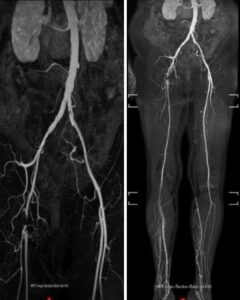

MR-Angiografiya (Şəkil 1):

- Sağ A. femoralis communis-in tam tutulmas

- AFS və APF kollaterallar vasitəsilə yenidən qanla dolu

- Aşağı hissədə yüksək dərəcəli daralmalar yoxdur, yaxşı üçdamarlı qan axını mövcuddu

- Sol tərəf: patologiya aşkar edilməyib

Şəkil 1.Çanaq və ayaq arteriyalarının MR-angiografiyası sağ A. femoralis communis-in tıxanmasını göstərir. A. femoralis superficialis və A. profunda femoris açıqdır.Sağ tərəfdə baldırın yuxarı hissəsində (proksimal hissəsində) üç damarla təchizat mövcuddur.Baldırın aşağı hissəsində (distal hissəsində) venoz strukturların üst-üstə düşməsi bu sahənin qiymətləndirilməsini məhdudlaşdırır.